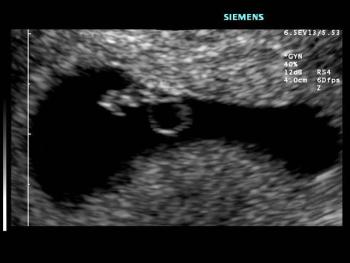

This is a confirmed case of scar ectopic pregnancy. Yesterday, I carried out this exam in an emergency room, without much time to perform an adequate sonogram, the patient did not feel good with “cramps” but no signs of bleeding.